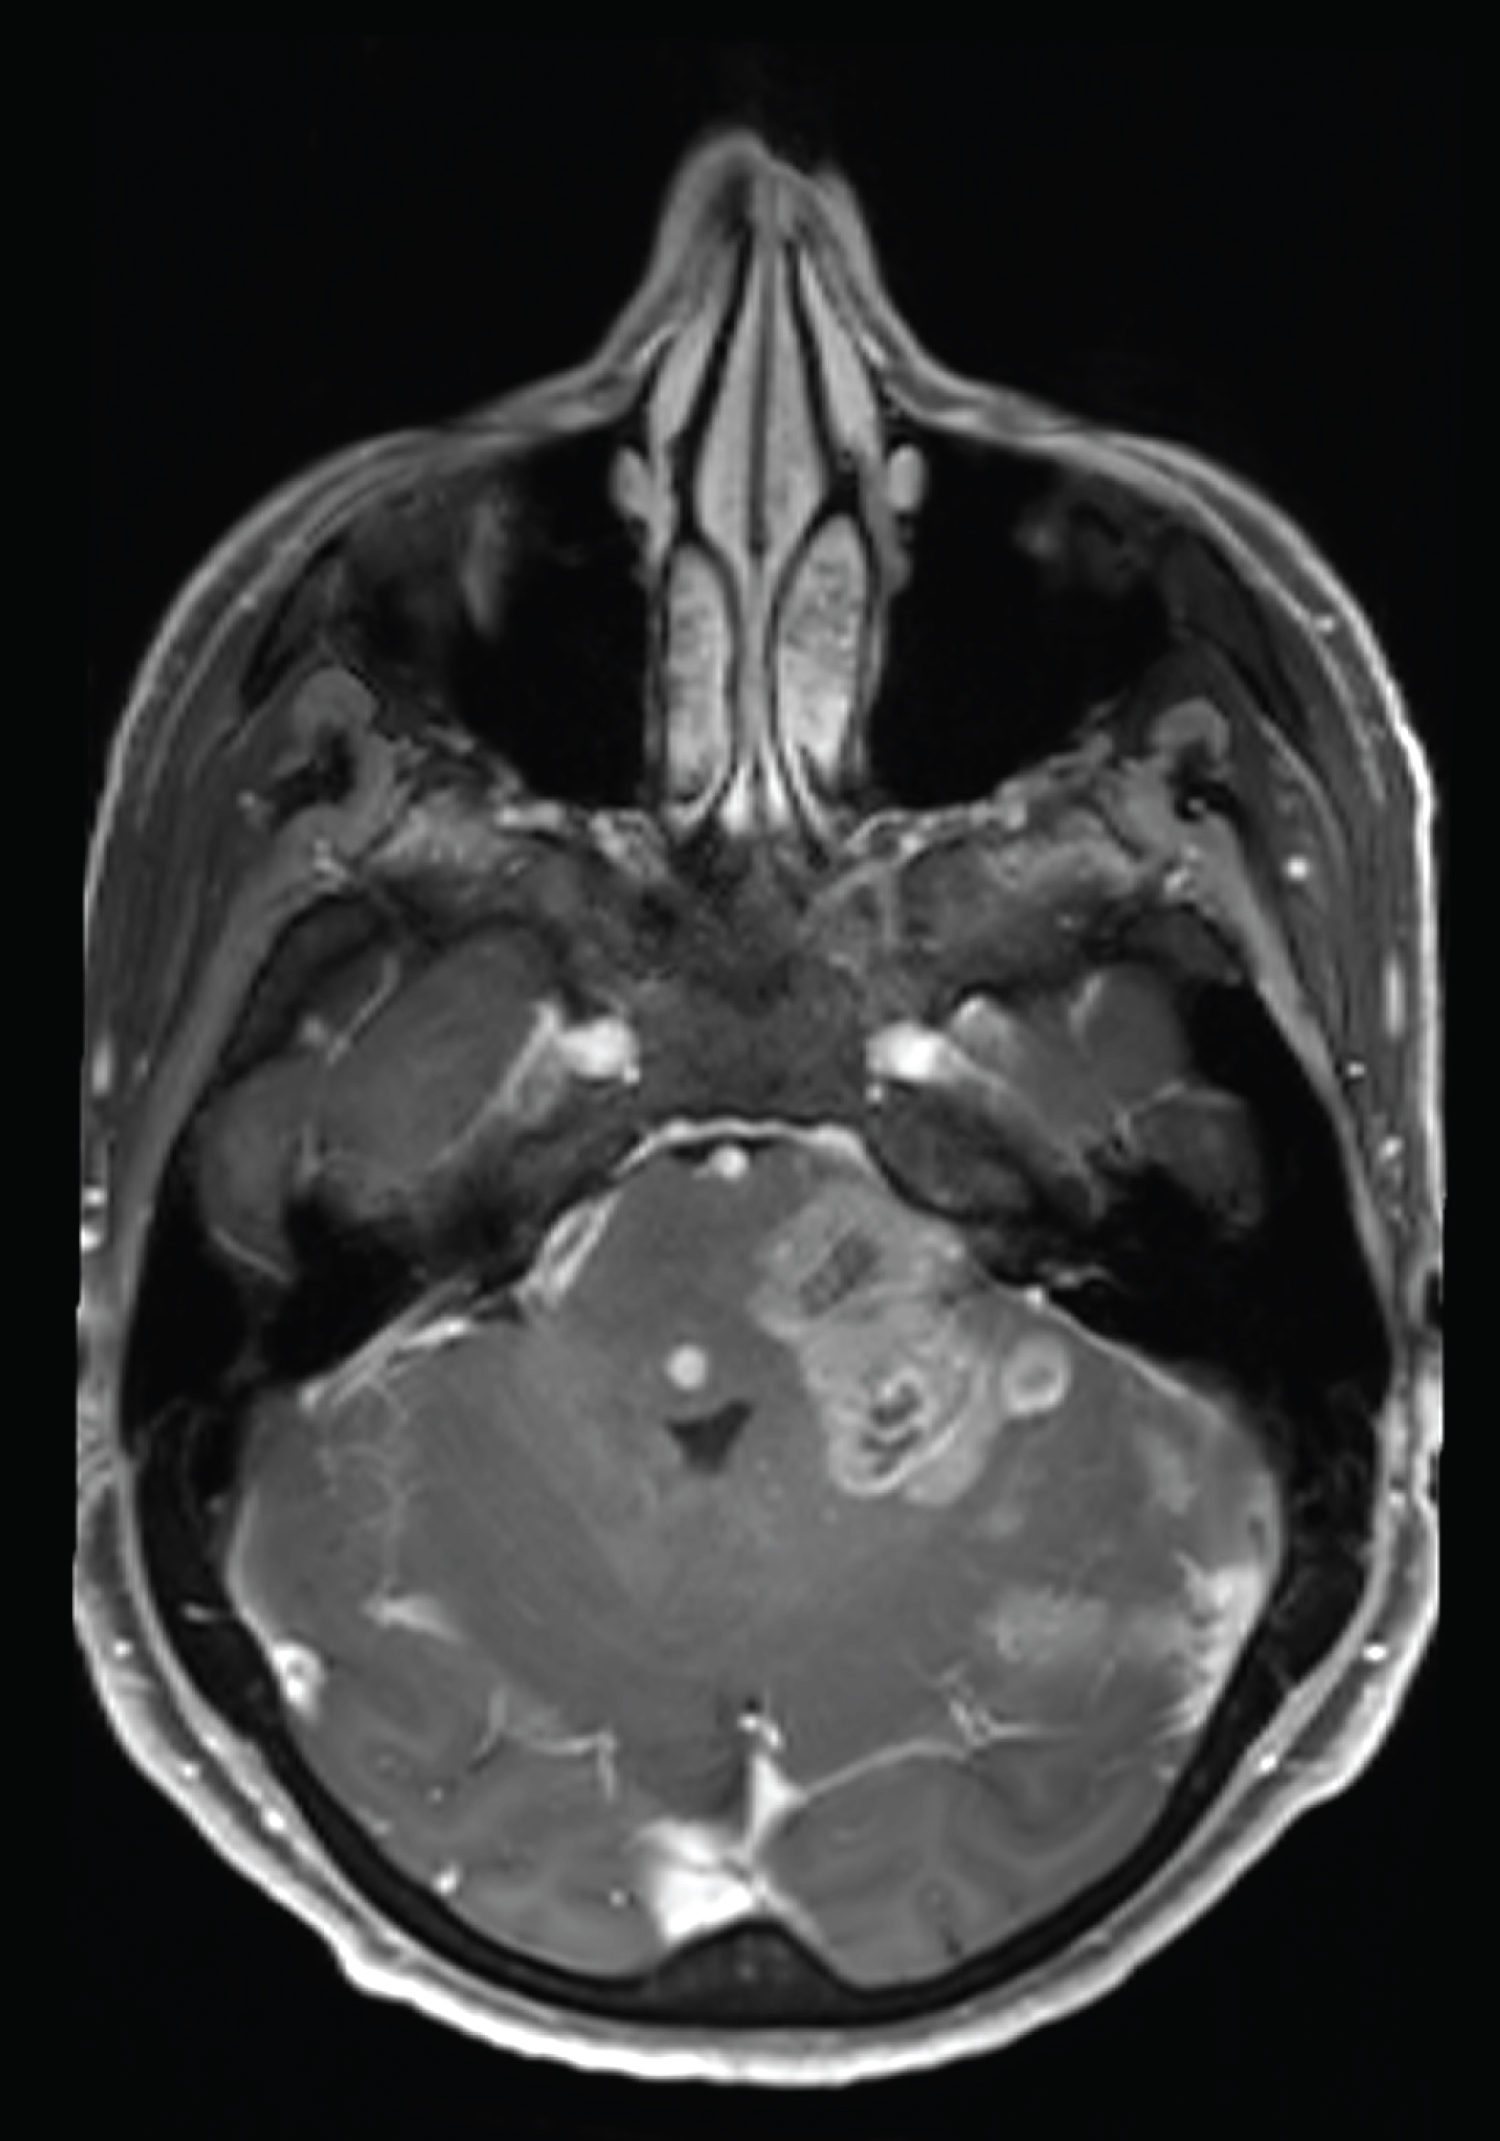

Second gadolinium enhanced brain MRI at 5 month clinical follow up (Figure 2) showed the appearance of multiple necrotic lesions of pons, midbrain and left cerebellar hemisphere, with rapid growth and confluence of lesions on MRI one month later (Figure 3).

Figure 2: MRI at 5-month follow up, with appearance of multiple necrotic lesions of pons, midbrain and left cerebellar hemisphere. View Figure 2

Figure 3: MRI at 6-month follow up, with rapid growth and confluence of lesions. View Figure 3